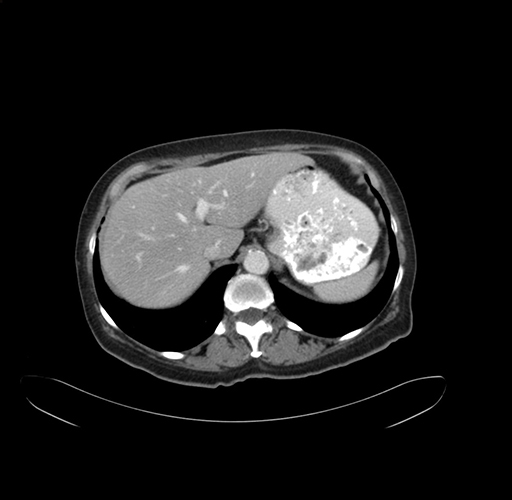

Pre-Chemo: Axial Venous

Axial Venous